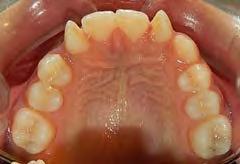

En la oclusal superior vemos la forma de la arcada que es oval con apiñamiento leve (Figura 4) y la inferior es cuadrada.

Estudios intraorales finales en las fotografías oclusales, se ven los laterales 12 y 22, así como la incorporación del canino al arco con torque adecuado (Figura 6). En la lateral derecha e izquierda la restauración estética de los laterales superiores,

Figura 4. Vista oclusal superior e inferior.